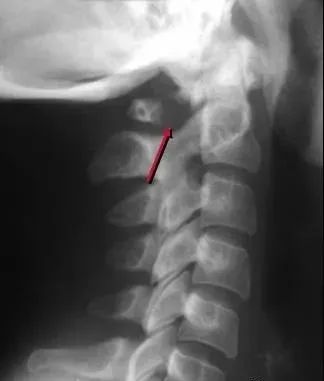

四、Hangman’s骨折

是C2最常见的骨折,也是最常见的颈椎骨折,多由过伸及压缩外力造成,骨折线经C2椎弓根,C2向前滑脱,不伴有神经损伤。

五、齿突骨折

多由过伸性损伤造成,常伴有C1向前滑脱,属于稳定性骨折。

另一患者